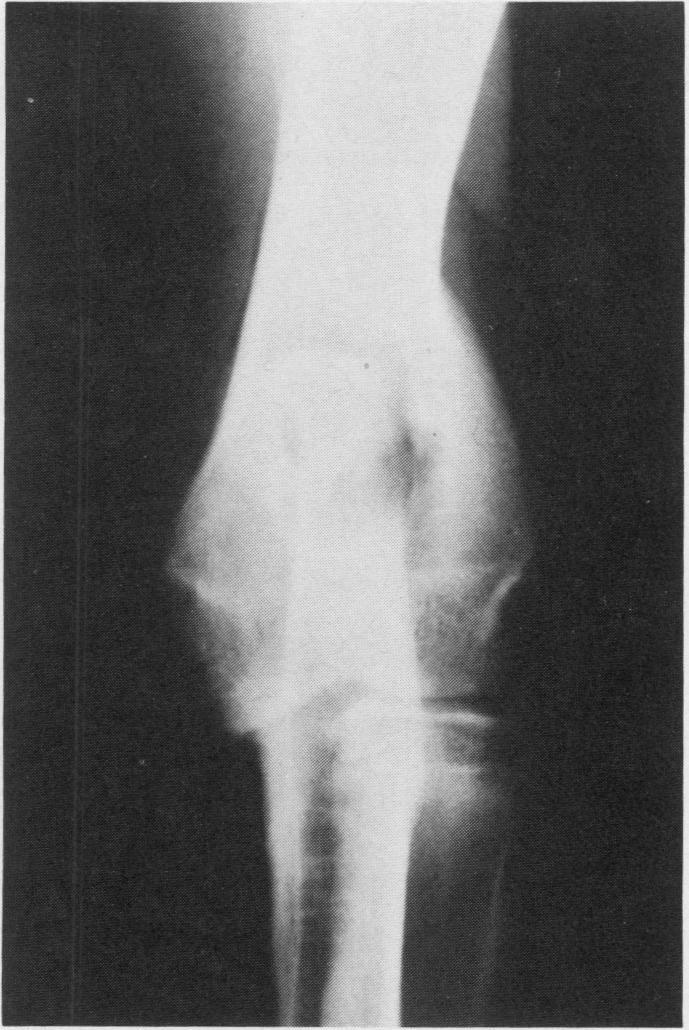

The presence of an ununited coronoid process, an ununited anconeal process and an ectopic proximolateral radial ossification center are described in a single elbow joint of a ten month old unspayed Great Dane. This animal and a nine month old spayed Saint Bernard, also with an ununited coronoid process, both had marked degenerative osteoarthritis associated with the instabilities.Chronic lameness and significant palpable elbow joint enlargement(s) were apparent in both dogs. Radiography was used to identify the lesions and surgical treatment produced satisfactory remission of signs.

在一只10个月大未绝育的大丹犬的单个肘关节中,发现了冠状突未愈合、肘突未愈合以及近端桡骨异位骨化中心。这只动物和一只9个月大已绝育的圣伯纳犬,同样有冠状突未愈合的情况,二者均有与关节不稳定相关的明显退行性骨关节炎。两只狗都有慢性跛行且肘关节明显肿大。通过放射摄影来识别病变,手术治疗使症状得到了令人满意的缓解。